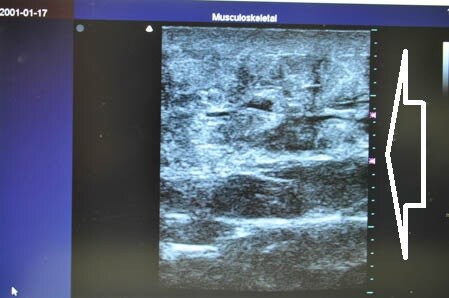

左腰。

↓ ↓ ↓

画像がしっかりと物語ってくれます。

きっちりと皮下脂肪を

根こそぎ!!

脂肪吸引しておきましたので